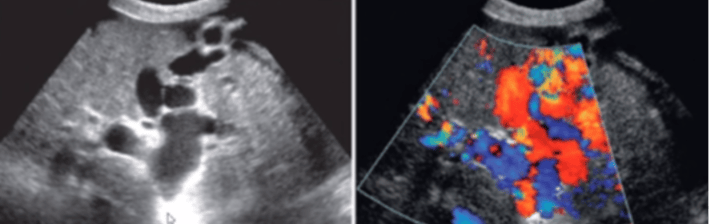

La ecografía doppler o eco-Doppler, emplea ultrasonidos y el efecto Doppler para poder visualizar la velocidad del flujo de los vasos sanguíneos